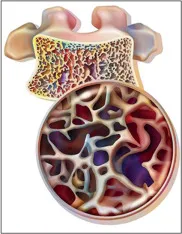

Amiloidose renal: aspectos sobre patogenia, diagnóstico e proteomica

Este vídeo apresenta, de forma didática e baseada em evidências, os principais achados da tese de doutorado sobre amiloidose renal, com foco em proteômica glomerular e ativação do complemento. São discutidos aspectos diagnósticos, implicações fisiopatológicas e correlações clínico-patológicas relevantes para a prática do nefrologista. O conteúdo sintetiza dados inéditos de matriz extracelular glomerular e diferencia perfis entre subtipos de amiloidose. Trata-se de um material aprofundado e acessível, ideal para atualização de especialistas na área.